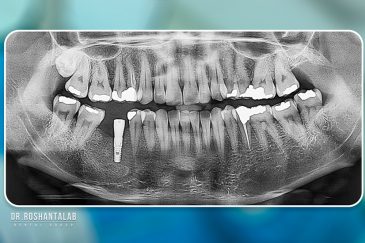

کلینیک تخصصی دکتر حسن روشن طلب با همکاری جمعی از متخصص ایمپلنت دندان و جراح فک و صورت بنام در حال فعالیت می باشد. این مجموعه مأموریت خود را ارائه خدمات تکمیلی دندانپزشکی در زمینه درمان های تخصصی و عمومی به شرح ذیل انجام می شود.

🔸جراحی پیشرفته نظیر سینوس لیفت

بهره مندی از دانش علمی و تجربه بالای موسس و جراحان این کلینیک، همچنین امکانات و تجهیزات به روز و کارآمد از جمله ویژگی های منحصر به فرد این کلینیک است. همچنین با ارائه خدمات درمانی با کیفیت و هزینه مناسب دندانپزشکی در رشت، تهران، اصفهان و استانبول ترکیه توانسته است در این سال ها لبخند رضایت بر صورت مراجعه کنندگان عزیزمان بگذارد.

انتخاب بهترین متخصص ایمپلنت که به تکنیکهای روز دنیا مسلط باشد، تضمینکننده سلامت فک و زیبایی لبخند شماست. در کلینیک دندانپزشکی دکتر روشنطلب، ما با بهرهگیری از تجهیزات دیجیتال در ۵ شعبه فعال (تهران، اصفهان، رشت و استانبول ترکیه)، خدمات تخصصی کاشت ایمپلنت دندان را برای بیمارانی که کیفیت و دقت برایشان اولویت دارد، ارائه میدهیم. در این متد، پروسه درمان با ظرافت بالا انجام شده؛ راهکاری ایدهآل برای کسانی که به دنبال درمان بدون درد با بالاترین نرخ موفقیت هستند.